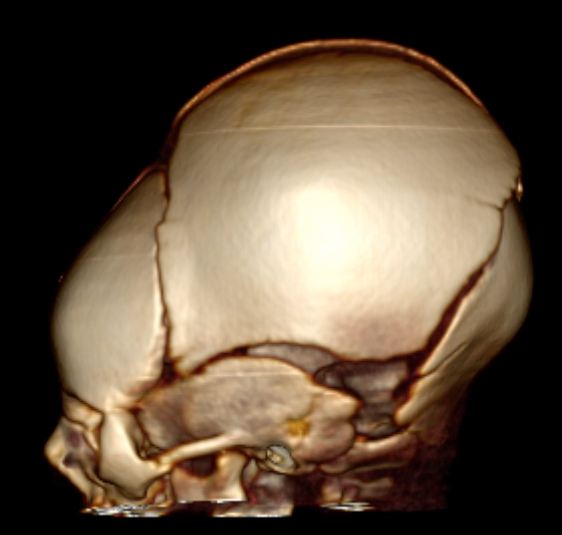

au cours de la naissance, naturelle aussi bien qu’instrumentale, l’os pariétal est soulevé, avec un enfoncement relatif de l’écaille occipitale (pseudo-embarrure au niveau du lambda Cf. ci-contre).

cette déformation (cranial moulding) peut persister quelques jours à quelques semaines en post-natal.